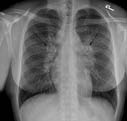

Posteroanterior chest on a normal female.